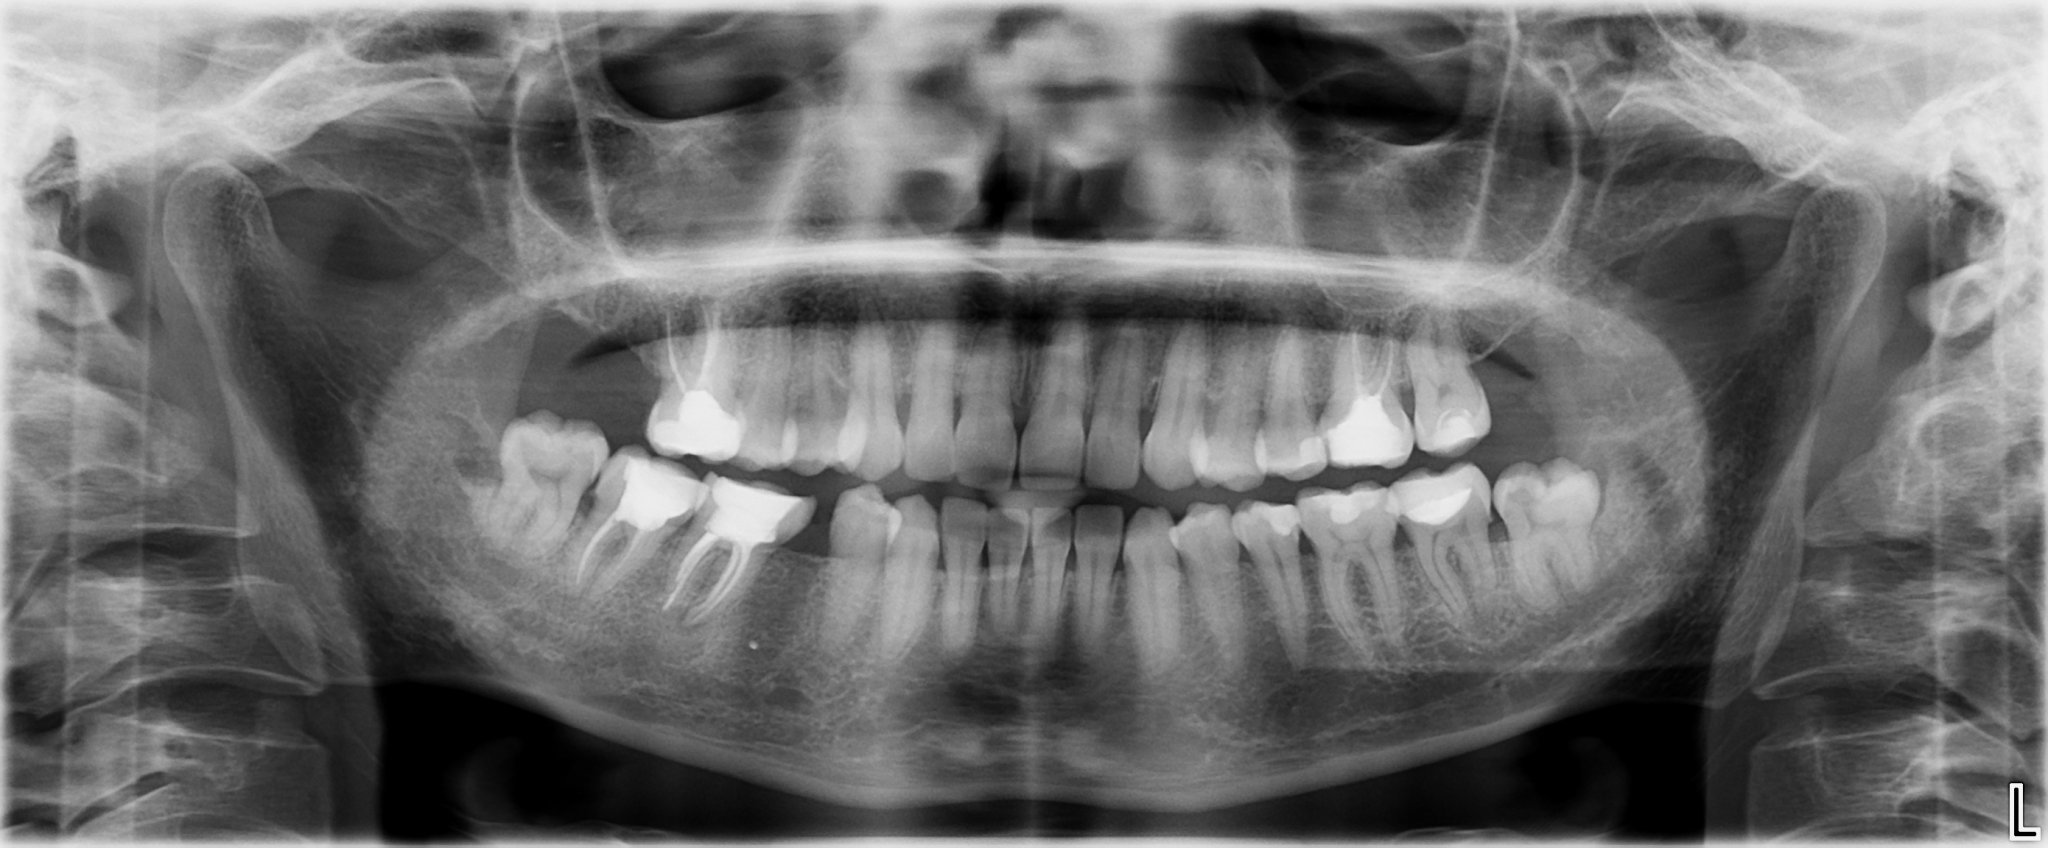

Хирургичното вадене на мъдрец се извършва, когато мъдреците са ретинирани или полегнали, което може да доведе до усложнения. Тази процедура изисква по-голяма прецизност и умения от страна на хирурга в сравнение с обикновеното изваждане на зъб. Хирургичното отстраняване може да бъде по-скъпо и да изисква по-дълго време за възстановяване.